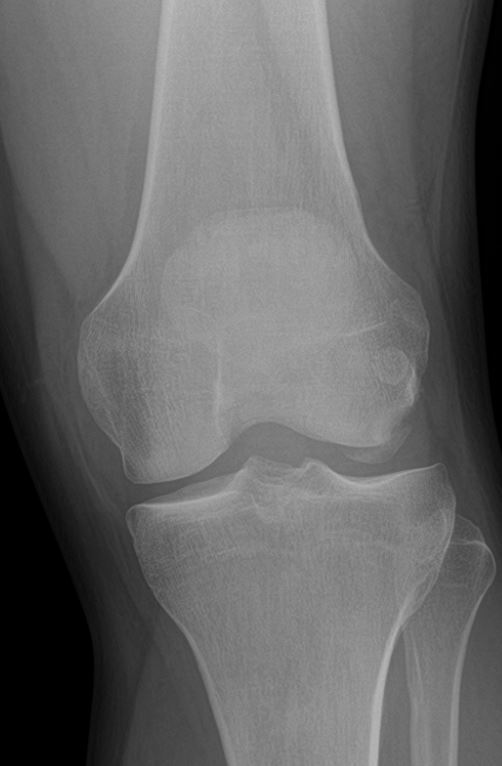

A healthy 37-year-old man sustained a knee injury after performing a deep flexion maneuver while playing a virtual reality game, with a VR headset on. His patella had dislocated laterally after he fell onto his knee whilst in deep flexion. There was no previous history of patella instability. On physical examination, the patient had a body mass index (BMI) of 33 and no signs of compartment syndrome. The patella was dislocated laterally, the knee was swollen, and tender over lateral distal femur. Radiographs of the left knee revealed a lipo-hemarthrosis and a large OCF of the lateral condyle of the femur (Figure 1 & 2). The patella was reduced in the emergency department and on repeat examination there was exquisite tenderness over proximal medial border of the patella in the area of the medial patella-femoral ligament (MPFL) attachment. Further tenderness was elicited over the lateral joint line. The patient was unable to straight leg raise and could hardly flex the knee to 30 degrees. The leg was placed in an extension splint and the patient was allowed non-weight-bearing on crutches.

Figure 1 AP Radiograph Left Knee.